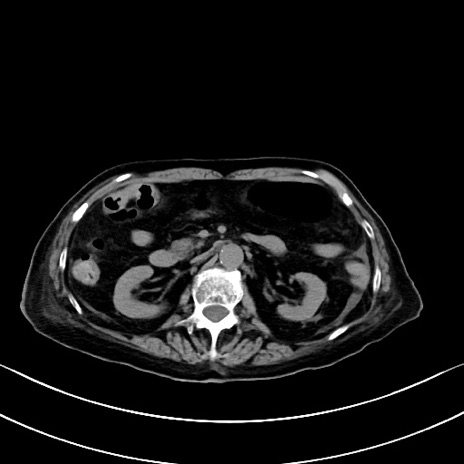

横断像

他院CT